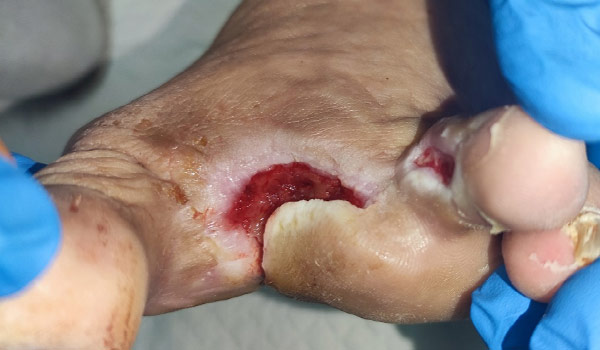

Osteomyelitis of IInd and IIIrd metatarsal bone after amputation, MRSA infection of bone, tendons and soft tissue

Only 7 days after treatment with Vulnamin Gel (also 7 days after reamputation), wound bed is covered with massive granulation tissue, skin margins are trying to close the wound naturally, no clinical signs of infection anymore.